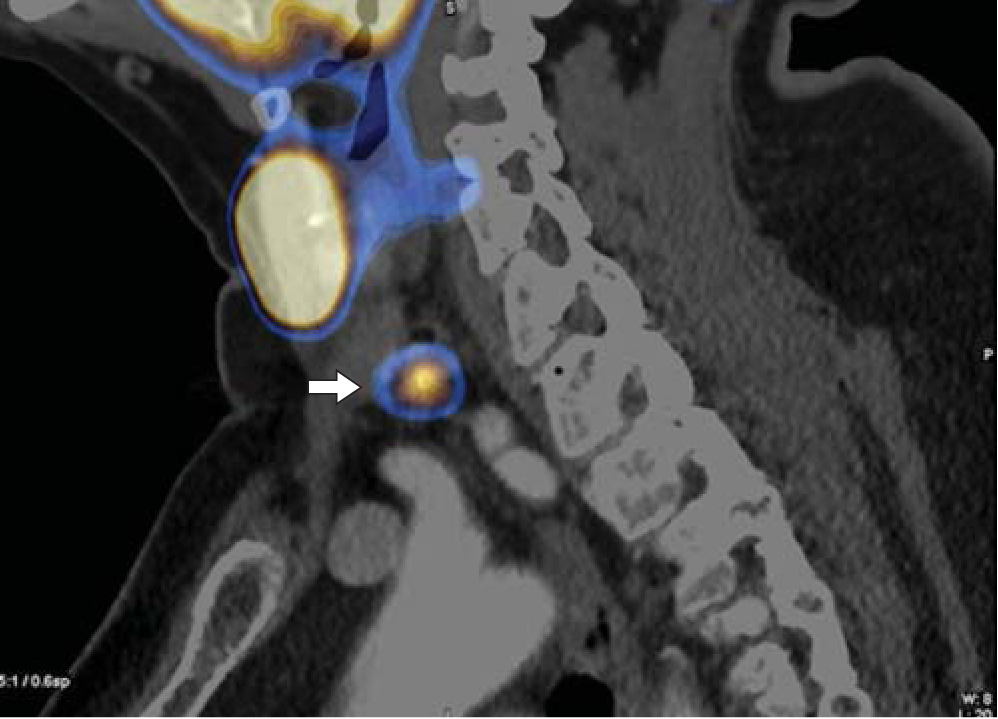

8. Fig. 7. SPECT / CT with 99mTc-MIBI, the formation of the thyroid gland behind and down from the lower pole of the left lobe of the thyroid gland (arrow), accumulating radiopharmaceuticals (images of MV Degtyarev, Research Center for Endocrinology). | |